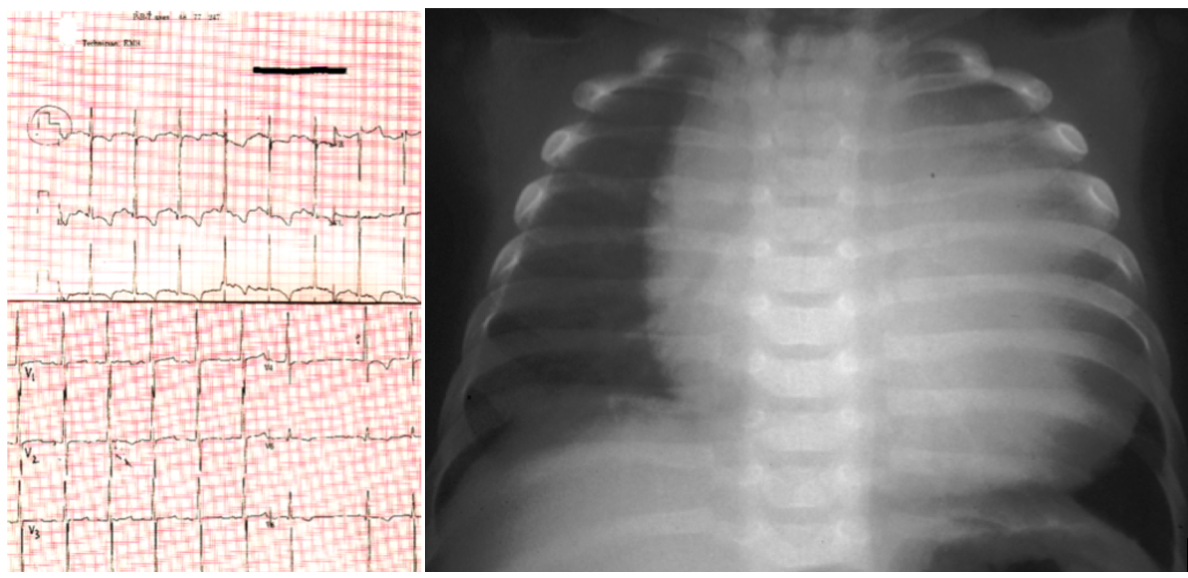

POMPE DISEASE

Metabolic disorder: Glycogen Storage Disease

Genetics: GAA gene

Inheritance: Autosomal Recessive

Clinical Features: Hypertrophic cardiomyopathy, FTT, severe hypotonia, short PR interval, macroglossia

Investigations: muscle biopsy (glycogen-containing vacuoles), ECG (shortened PR, large QRS), enzyme studies, gene studies, urine hex4 (tetrasaccharide) - level correlates with severity

Management: Enzyme replacement therapy